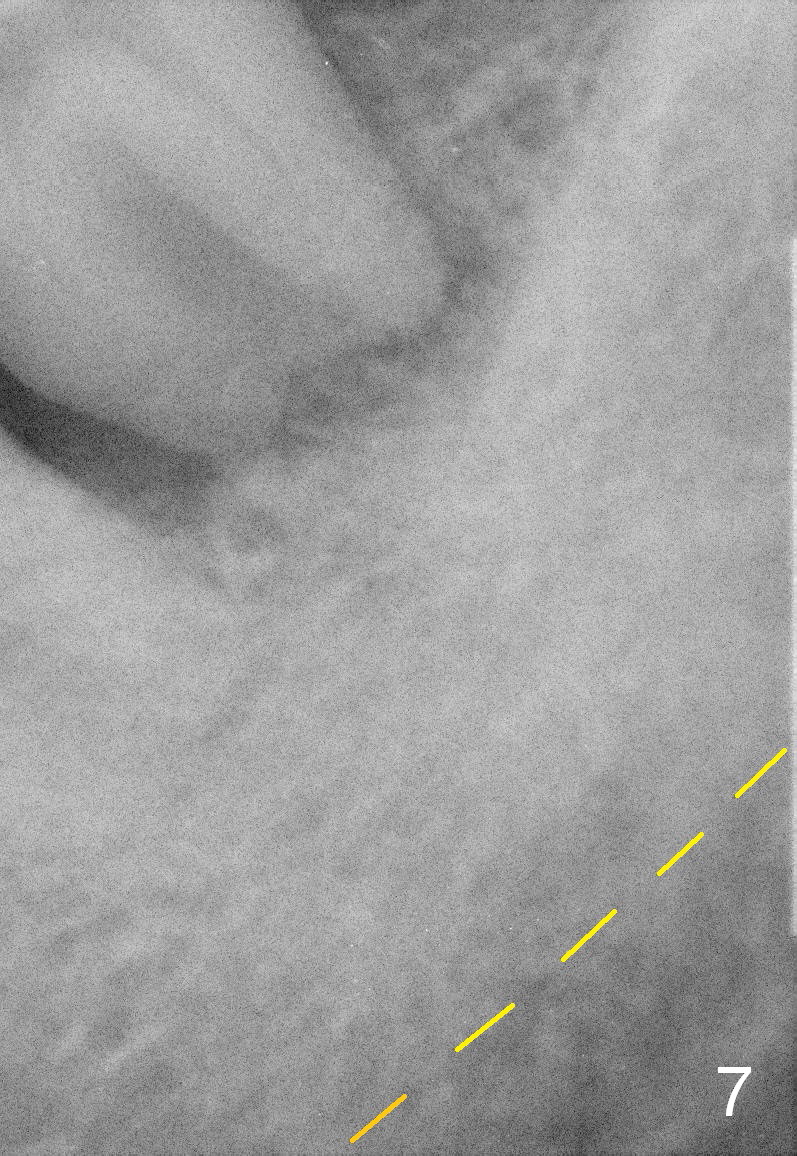

A 63-year-old man has periodontitis. The tooth #18 (probably 17) has mobility III (Fig.1). Three more PAs are taken with deeper placement of #2 sensor (Fig.2,6,7) to show the upper border of the Inferior Alveolar Canal (yellow dashed lines). The affected tooth has severe bone loss, especially mesially (Fig.2,3 (arrowheads)). No matter whether bone (Fig.4) or gingiva (Fig.5)-level implant is placed, the threads should be covered circumferentially by bone, native or grafted (red circles). In Fig.5, the threads are apical to black arrowheads, whereas the rough surface, which should be also contacted by bone, is the lower half above the black arrowheads.